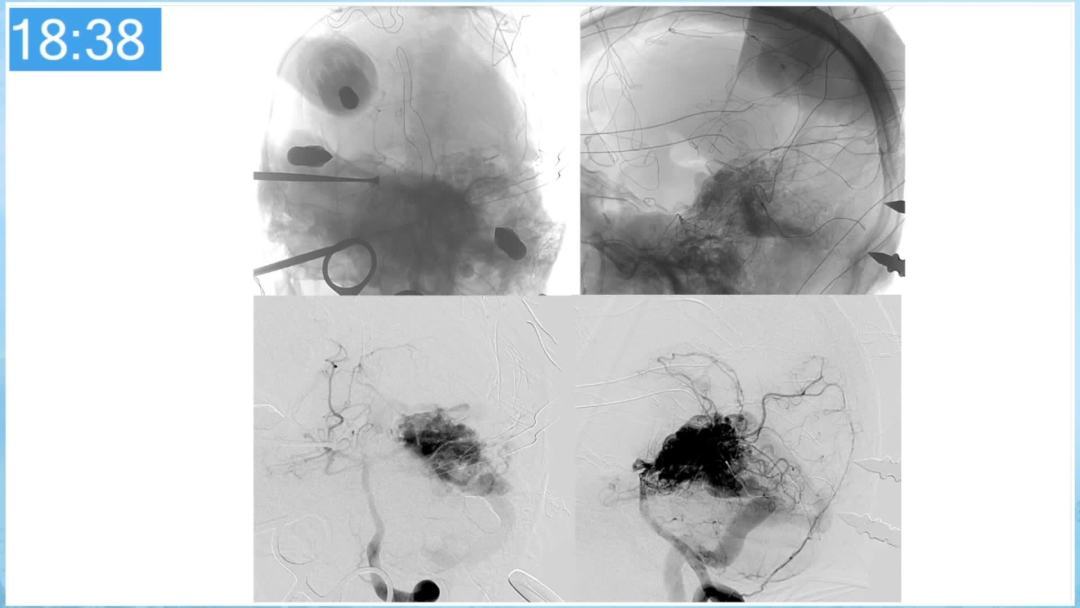

合理的复合平台下的综合治疗,针对每一个病变对应不同方法安全性分析,不预设、不排斥,每种技术发挥到最佳,互相保障。